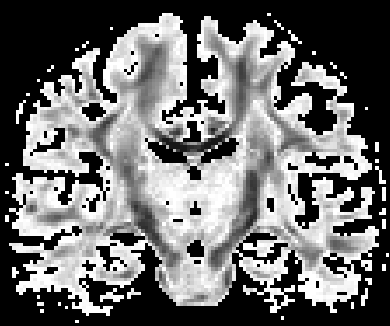

Non-negative spherical deconvolution (NNSD) (Cheng et al., 2014) is performed to estimate non-negative fiber ODFs from three-shell DWI data. NNSD works for multi-shell data. It is more robust to noise, and the obtained fiber ODFs (fODFs) in isotropic regions are closer to the isotropic spherical PDF, compared with conventional constrained spherical deconvolution (Tournier et al., 2007). After obtaining the fODFs by NNSD, the peaks are detected from the estimated fODFs with GFA larger than , as described in Section 3.4. OO and OD are calculated from the spherical harmonic representation of fODFs along their principal peaks as shown in Algorithm 1. The second row in Fig. 11 demonstrates FA from tensors estimated by DTI, OO and OD from fODFs estimated by NNSD, and the total distortion map estimated from the local orthogonal frames of fODFs. Fig. 12 and 13 show the close-up views of fODFs, local orthogonal frames, and the six proposed indices for the red and blue regions in Fig. 11, where the region shown in 12 is also visualized in the DFA pipeline in Fig. 1. The fODF glyphs are colored by using its sampled directions. The three orientations in the local orthogonal frame in each voxel are visualized by using three tubes in red, green, and blue colors respectively. There is no local orthogonal frame in some voxels because those voxels have GFA values lower than . These figures show the following: 1) OO is high in anisotropic areas with well-aligned directions, while OD is high in isotropic or crossing areas. 2) The four orientational distortion indices are low in areas with well aligned principal directions, and zero in isotropic voxels without peaks. Distortion indices are high in voxels where the principal directions in its local neighborhood change largely. 3) The central voxels in red region is the crossing area of the Corpus Callosum from left to right and Fornix that goes through the coronal slice. The twist index showed high value in this crossing area as expected.